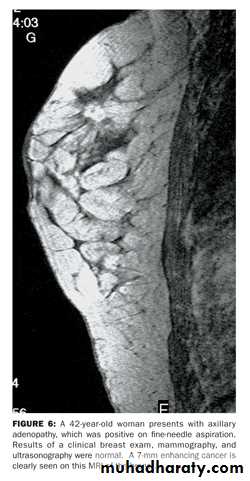

c-magnetic resonance useful in symptomatic patient with breast implant where US is not diagnostic and also used in to detect local recurrence where US and mammography are un helpful